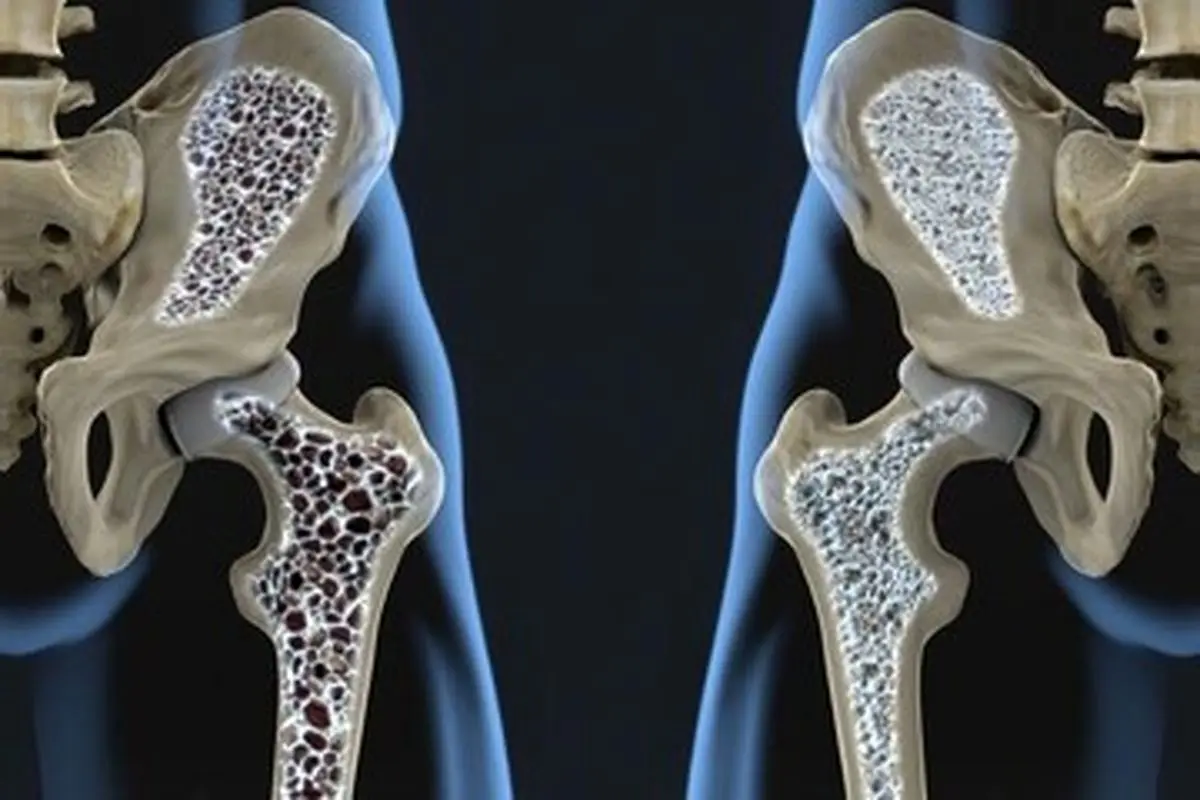

ویتامین D خطر ابتلا به پوکی و نرمی استخوان را کاهش میدهد.

به گزارش پارسینه و به نقل از تسنیم، ویتامین D یک ویتامین محلول در چربی است که بر طبق پژوهشهای مرکز مطالعات ستون فقرات سلولهای جدید استخوان را تولید میکند، استخوانهایتان را سالم و قوی نگه میدارد، به جذب کلسیم کمک میکند، خطر ابتلا به پوکی و نرمی استخوان را کاهش میدهد، از التهاب بدنتان میکاهد و درد ناحیهی کمرتان را تسکین میدهد.